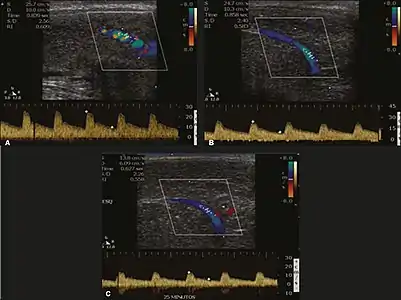

醫學超音波檢查

多普勒超音波检查可用以檢驗陰莖在勃起後的狀態。大部分器質性勃起功能障碍跟陰莖海綿體的血流改變有關,當中又以動脈阻塞性疾病為代表,其大多因動脈粥樣硬化所致;靜脈閉塞機制失效也會引致血流改變。在多普勒超聲檢查之前,應以B模式檢查陰莖,以此甄別其有沒出現腫瘤、纤维斑块、钙化、血肿,以及評估海绵體动脉的形態,以此推測其判斷其是否出現曲折或動脈粥樣硬化的情況。[26]

可通過注射10-20µg的前列腺素E1來誘使陰莖勃起,隨後在接下來的25-30分鐘內每5分鐘檢查動脈血流一次。前列腺素E1對於易感陰莖異常勃起(例如鐮狀細胞貧血症患者)、陰莖解剖畸形、已植入陰莖假體的患者而言是禁忌的。此外通常也會施用2mg的苄胺唑啉。在此之上若配合視覺和触覺刺激,效果便會更佳。一些著者建議在求診者伴發禁忌症的情況下,以口服西地那非來代替注射藥物,但此建議的效果仍存有爭議。[26]

在注射上述药物之前,血流模式具有单相、低收縮期流速、舒张期流動欠奉的特點。在注射药物後,可預計收縮期和舒张期的最大流速會上升,然後舒张期流速會因靜脈漸漸閉塞而減少,當陰莖變得堅硬時相關結果更會呈陰性。不同研究給出了不同的動脈血流流速參考值,從>25cm/s至>35cm/s不等。若大於35cm/s,則顯示當事人沒患上動脈疾病;若少於25cm/s,則表示動脈供血不足;若介乎25cm/s-35cm/s之間,結果會因欠顯著性而不能太確定是何者。獲得的數據應與所觀察到的勃起程度畫上聯繫。如果收縮期最大流速正常,則應評估最終的舒張期流速。大於5cm/s的舒張期流速跟靜脈性勃起功能障碍有關。[26]